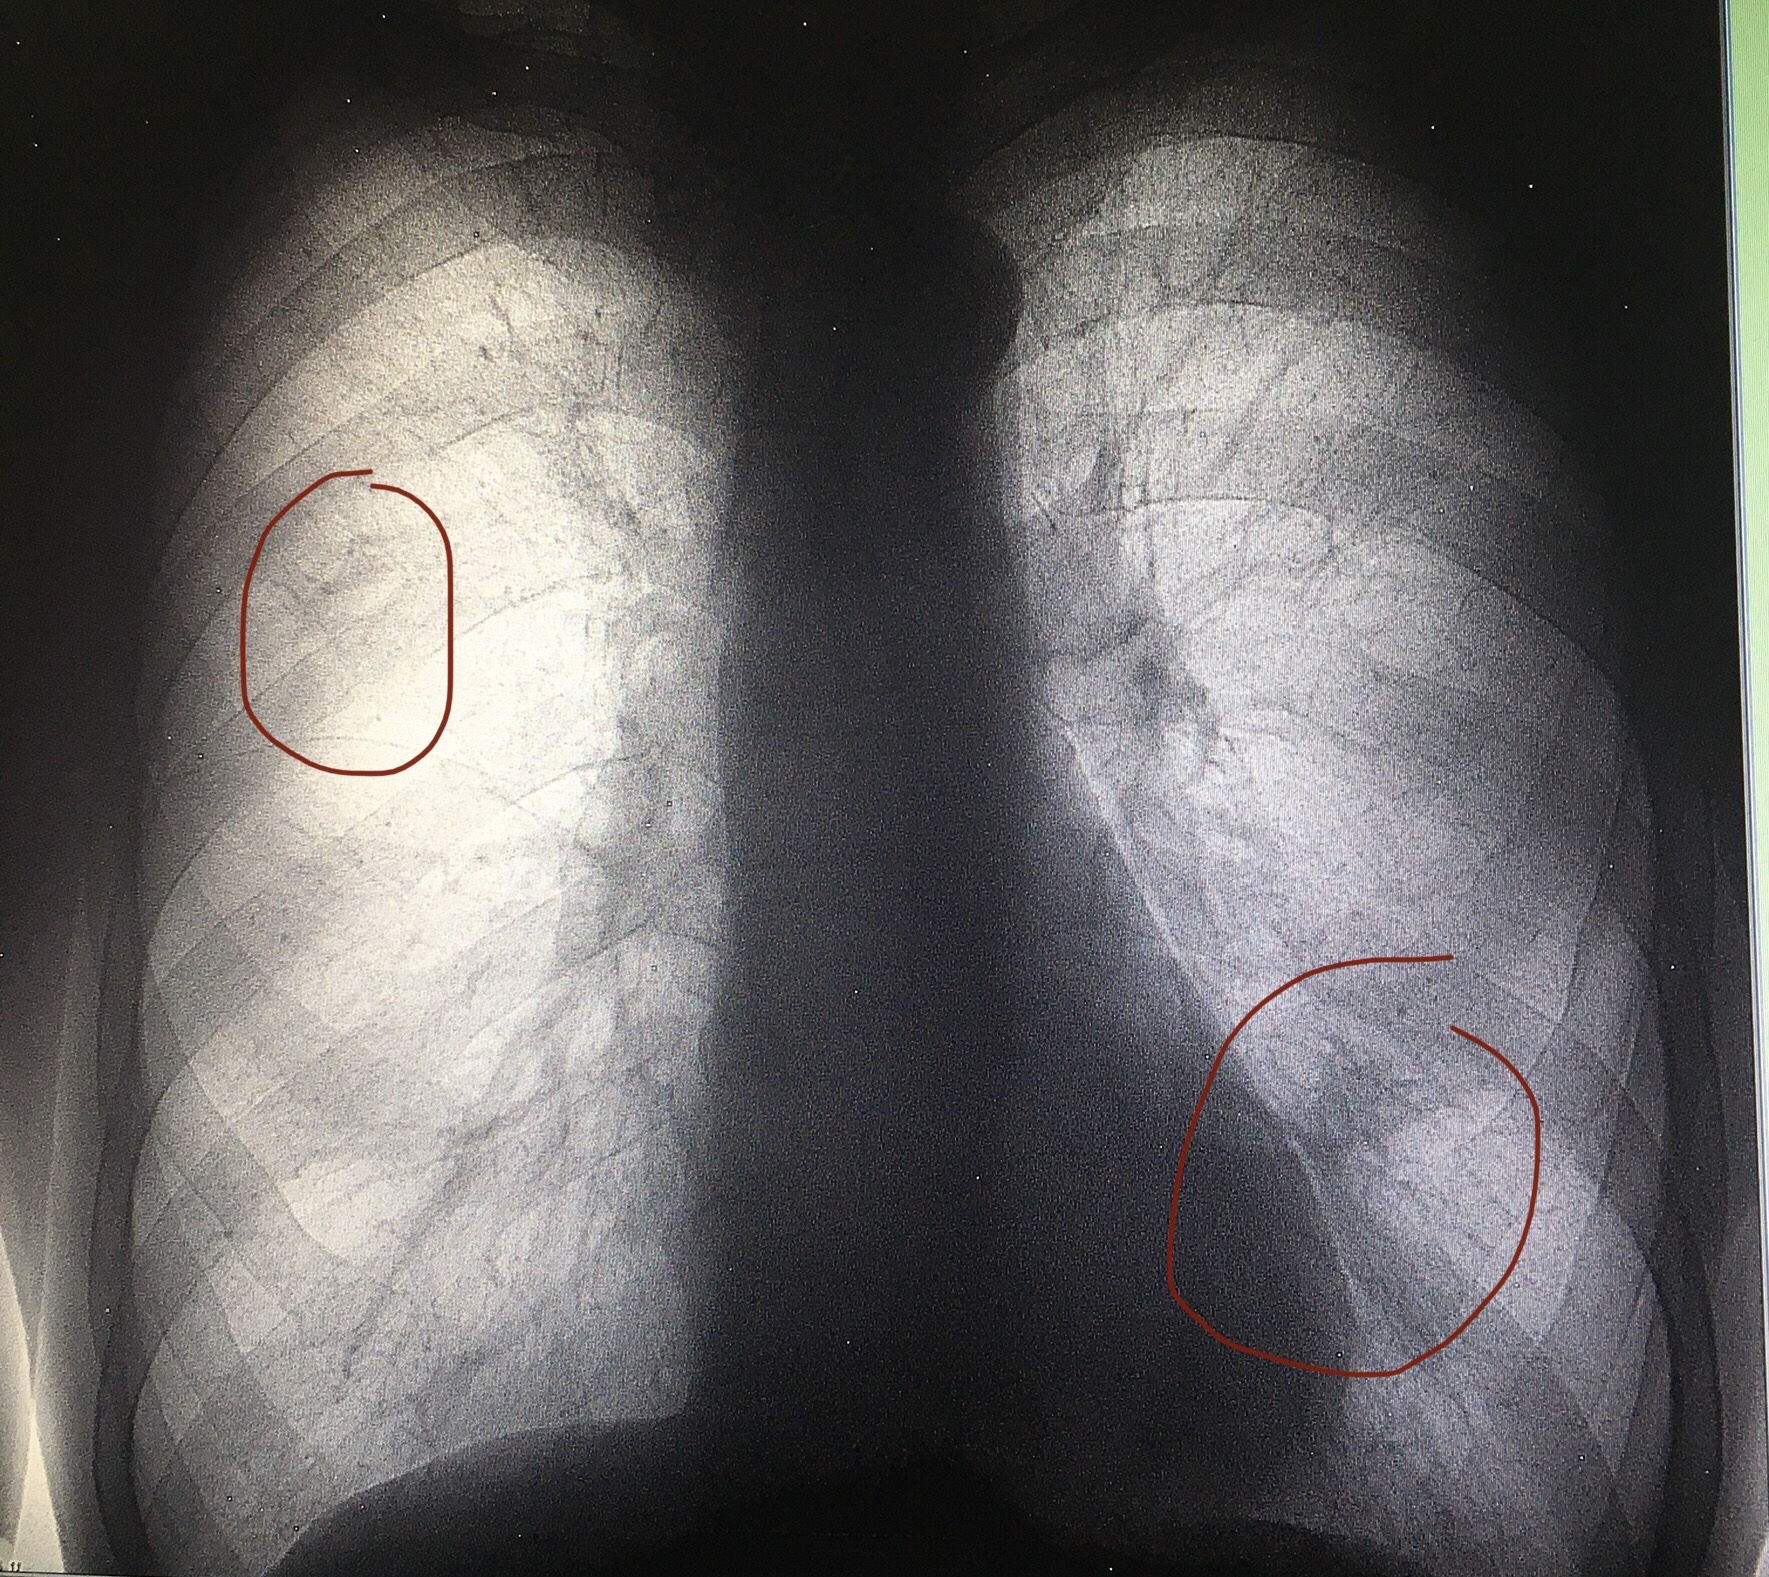

Снимок легких при туберкулезе является важным методом диагностики этого заболевания. На рентгеновских снимках можно увидеть изменения в легких, которые свойственны туберкулезу.

Фотографии снимков легких при туберкулезе

В данной статье представлены многочисленные фотографии снимков легких при туберкулезе, чтобы помочь вам понять, как выглядят изменения легких на рентгеновских снимках при этом заболевании.